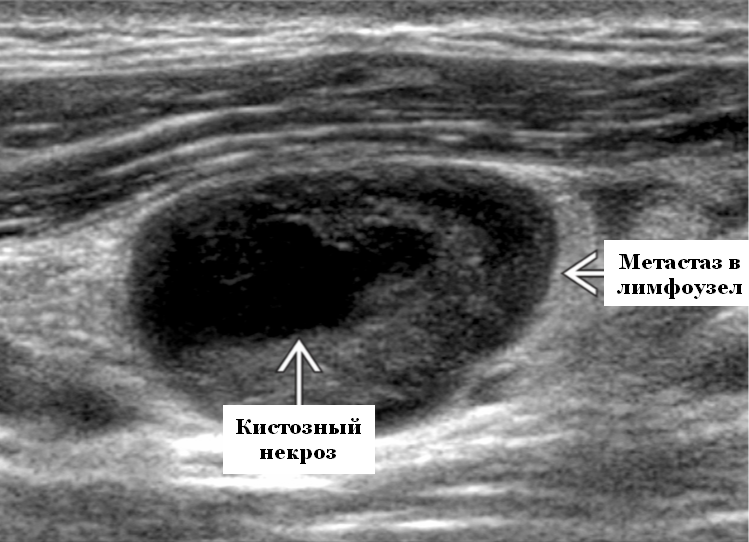

- УЗИ лимфоузлов — позволяет оценить их структуру и размеры

После обнаружения подозрительных лимфоузлов, их пунктируют или проводят биопсию. Полученный материал отправляют в лабораторию на гистологическое или цитологическое исследование. Только после лабораторного подтверждения можно достоверно говорить о наличии метастазов.